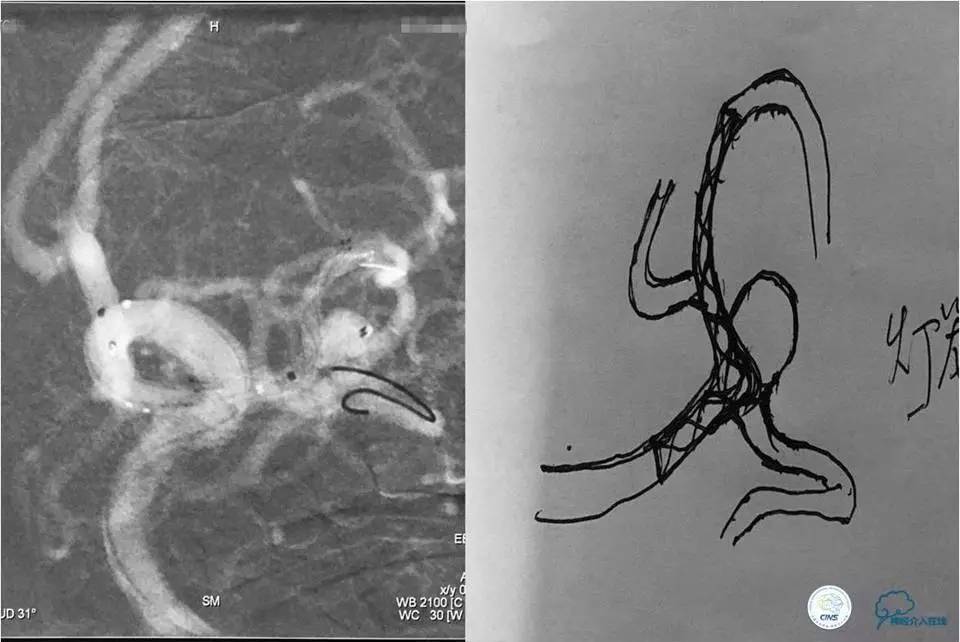

左侧颈内动脉三维旋转后选取工作位角度造影:左侧大脑中动脉分叉部宽颈动脉瘤,大小约8.13mm×7.45mm,瘤颈5.35mm,且上有籽瘤。

将Traxcess14引导Headway17准备送入下干,微导丝能够顺利进入下干,但微导管无法跟进,被LVIS JR支架网丝卡住,此时发现支架变形,呈灯笼状完全覆盖下干。

工作位造影

Traxess14微导丝携带Echelon10直头微导管穿过LVIS JR支架网孔进入瘤腔内,送入弹簧圈数枚并解脱,直至造影显示动脉瘤完全栓塞,解脱左后1枚弹簧圈。行工作位及标准正侧位造影。